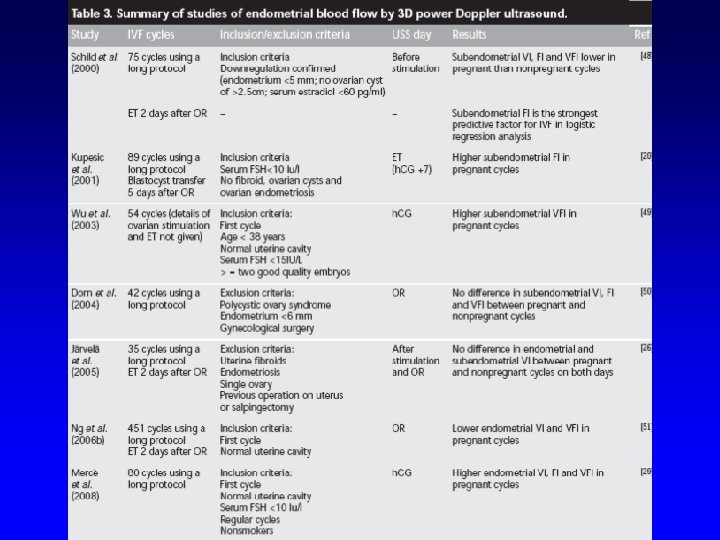

Endometrial receptivity Endometrial thickness and volume Endometrial pattern Doppler study of uterine vessels Endometrial and subendometrial vessels 1. 2. 3. 4. • • 2 D Doppler flow indices 3 D Power Doppler indices: objective assessment of the blood flow towards endometrial and subendometrial regions

Endometrial blood flow l. A good blood supply towards the endometrium is essential for normal implantation.

Endometrial volume and blood flow Subendometrial shell volume and blood flow